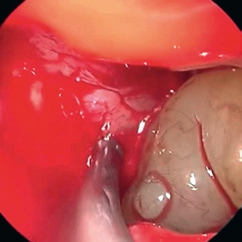

Bei anhaltender klinischer Symptomatik nach erfolgter Zahnbehandlung sollten gegebenenfalls eine rhinochirurgische Behandlung zur Verbesserung der maxillären Clearance und Entfernung des entzündlichen Débris aus der Höhle über einen erweiterten supraturbinalen Zugang eingeleitet werden. Kritisch sind überstopfte Füllmaterialien, da diese gehäuft zur Ausbildung von Pilzkugeln in der KH führen. Histologisch werden dabei überwiegend Pilzhyphen und typische Fruchtköpfe gefunden. Mikrobiologisch lassen sich meist Aspergillus-Stämme nachweisen. Charakteristisch ist die Kalzifizierung der Pilzhyphen, die bei einer Verdichtung kalkdichte Konkremente bilden und als Rhinolithen im CT oder DVT erkennbar werden (Abb. 10) [14]. Einer chirurgischen Sanierung durch vollständige Entfernung des Pilzmaterials über einen erweiterten endonasalen Zugangsweg ist hier der Vorrang einzuräumen [15]. Die Erfolgsrate nach diesen Behandlungen kann als sehr hoch eingeschätzt werden (Abb. 11a und b).